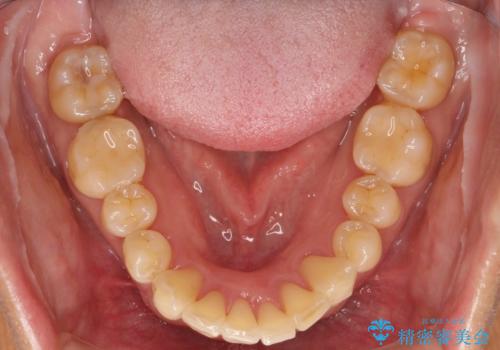

- 全体的なガタガタと前歯をきれいにしたいとのことで来院されました。

下の歯は重度のガタガタがあり、上の前歯は何本かが神経の治療がしてある状態でした。

インビザラインにて歯並びを整え、上顎の前歯にセラミックを装着する計画としました。